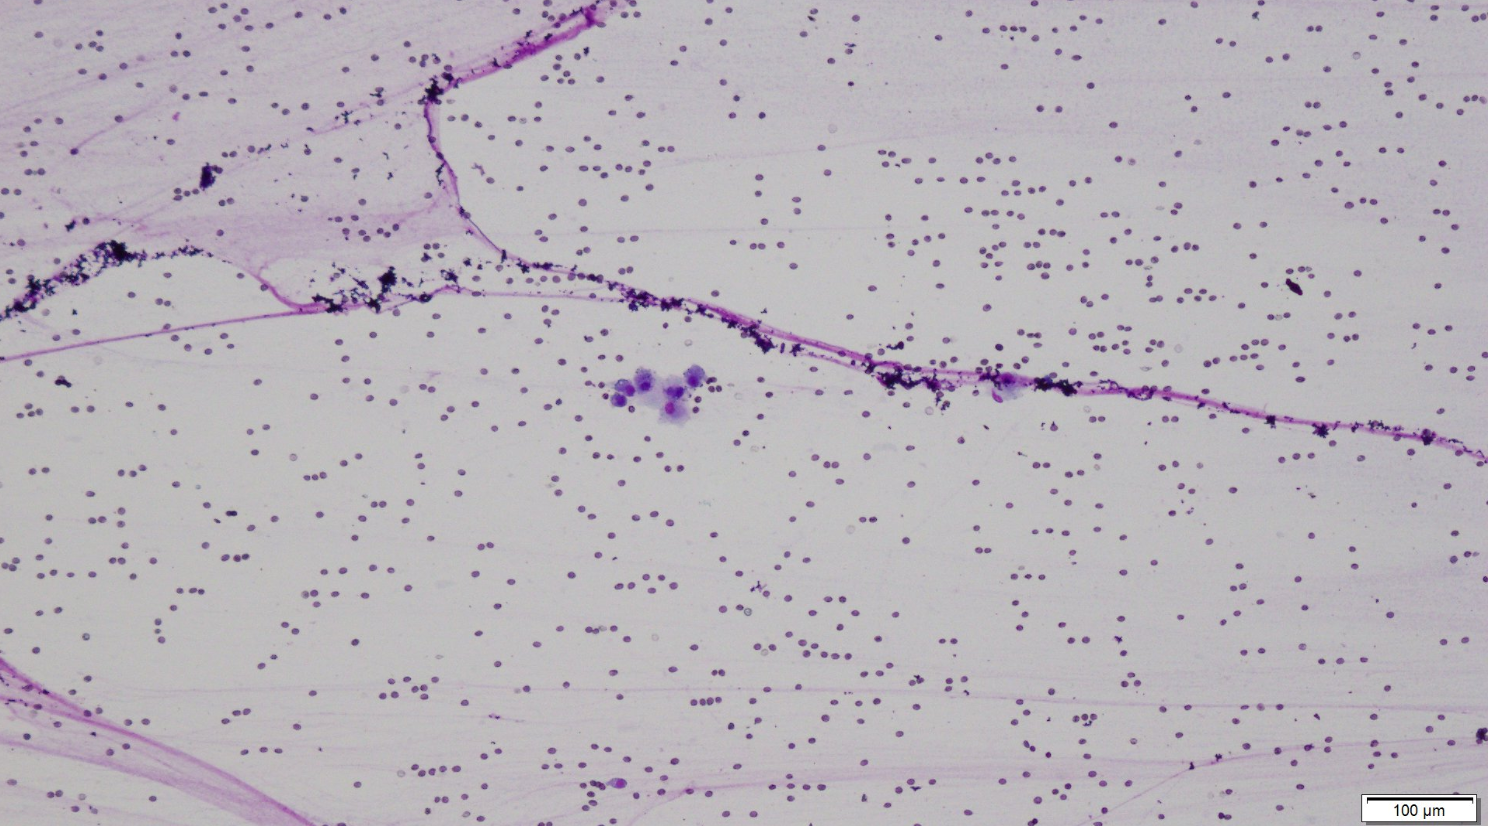

Below is an image of the synovial fluid from this dog. Which features indicate that the fluid has high viscosity? (You may select more than one option.)

This is called “windrowing” and refers to the rows [windrows] of cells formed.